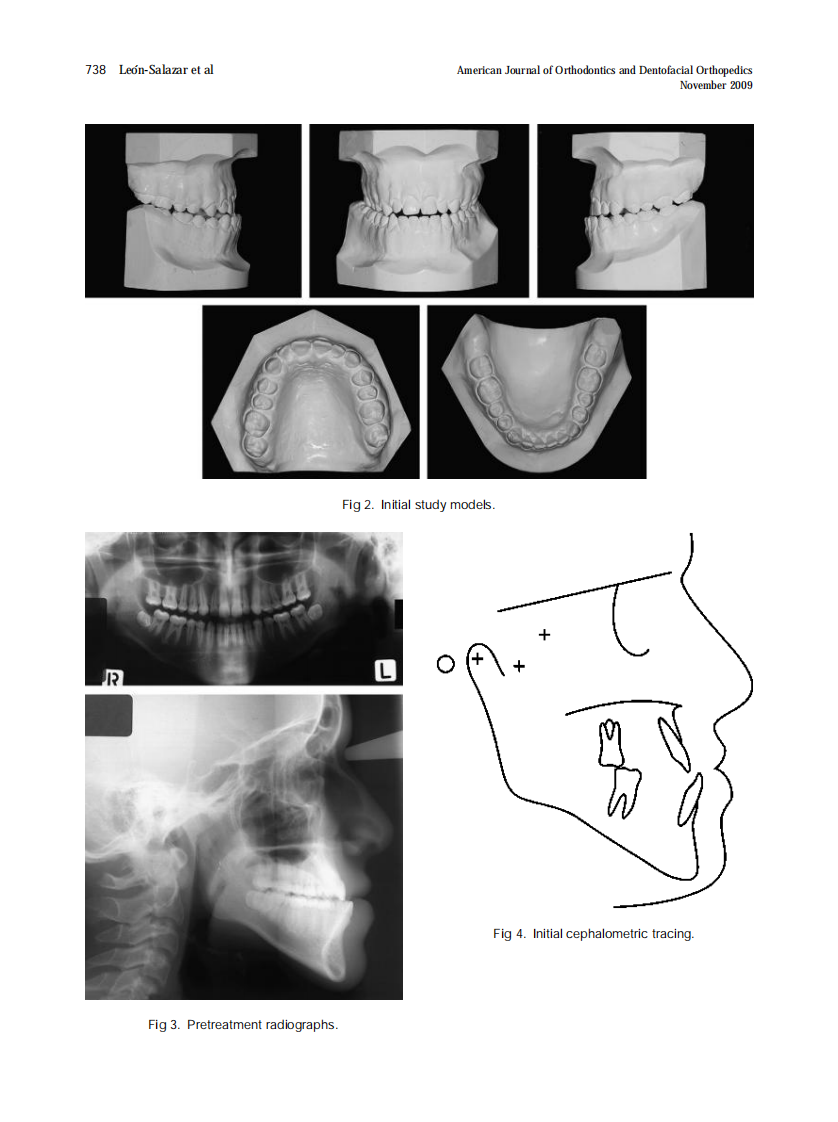

AJO-DO

2009_136_5_736_745.pdf